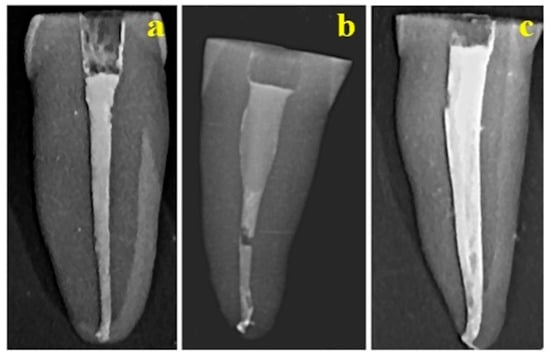

Radiologic images of the endodontic fillings are displayed in Figure 1. In the single-cone (SC) obturation technique, the gutta-percha cone exhibits intimate adaptation to the canal walls through a uniform and thin layer of endodontic cement, thereby ensuring a hermetic seal and optimal dentin adhesion (Figure 1a).

Figure 1. Radiographs of root canal fillings performed using the following methods: (a) SC technique, (b) WVC technique, and (c) LC technique.

The warm vertical compaction (WVC) specimens demonstrated extensive gutta-percha penetration into canal irregularities and superior interfacial adhesion; radiographic evaluation confirmed a continuous obturation with only minor discrepancies, such as a localized discontinuity in the median third and apical constriction, both of which merit further structural analysis (Figure 1b). In contrast, samples obturated using the lateral condensation (LC) technique displayed satisfactory gutta-percha adaptation and adhesion to dentin, accompanied by minor surface abrasions and halo-like formations. Nonetheless, the presence of possible micro cracks or discontinuities within the sealer layer suggests a potential for microleakage, underscoring the need for an advanced microscopic assessment to elucidate the extent of these defects (Figure 1c).